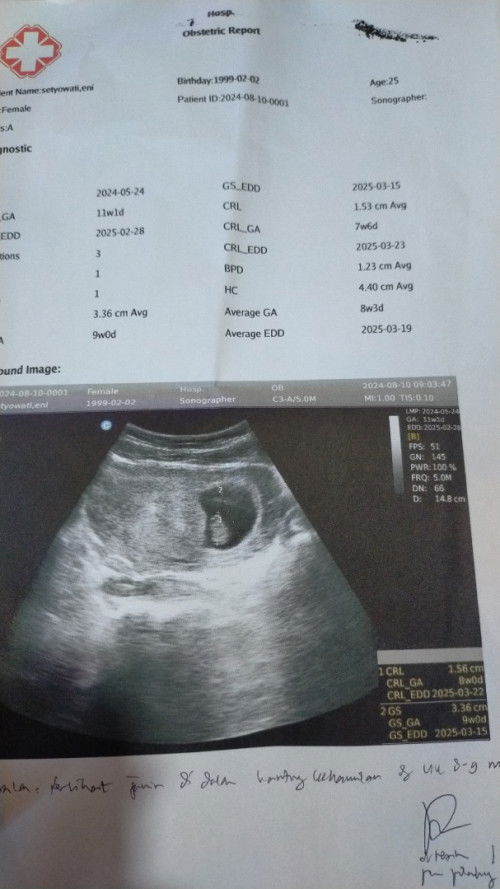

11week tapi USG 9week

Bun ada yang sama nggak kalo HPHT 11 week tapi USG baru 9week udah kelihatan janin nya tapi kok beda 2minggu ya soalnya siklus juga ga teratur, dan kontrol lagi perkembangan nya gmna Bun sharing dong , normal gak ya Bun ya